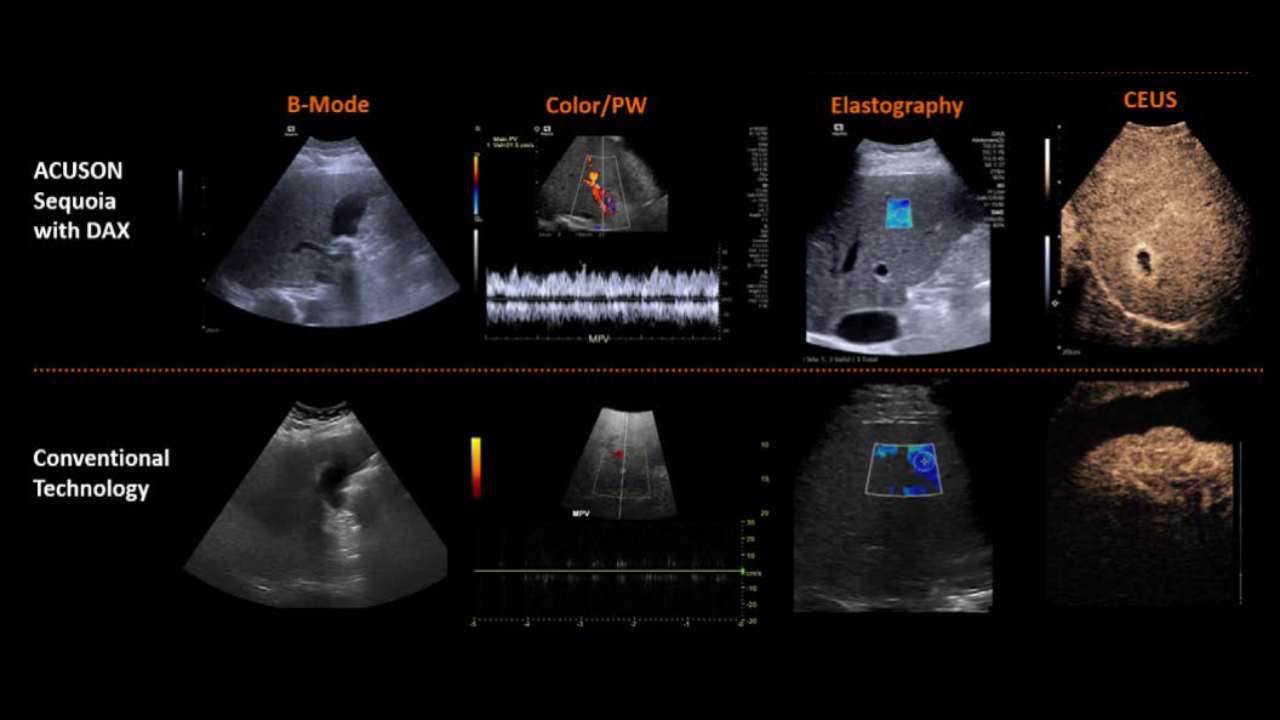

Every patient deserves a definitive ultrasound, even when the exam is difficult. The DAX Deep Abdominal transducer for ACUSON Sequoia brings clarity at depth and consistent visualization of deep anatomy while reducing the force needed to scan.

In high-BMI and technically challenging cases, it helps elevate B-mode and Doppler performance and works seamlessly with advanced applications such as shear wave elastography, Ultrasound-derived Fat Fraction, and contrast-enhanced ultrasound. The result is a gentler exam, clearer answers, and decisions made with confidence.